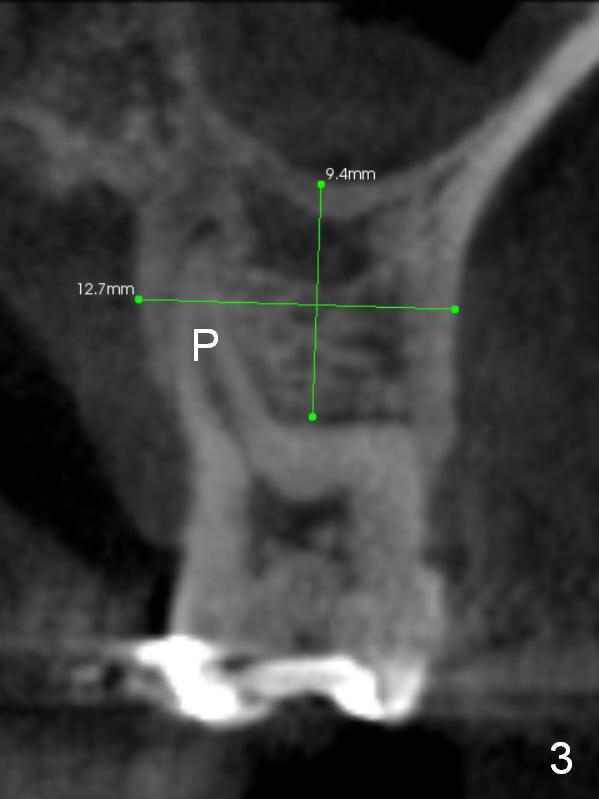

It is noteworthy that the tooth #14 was less affected than #15 22 months earlier (Fig.1 (CBCT sagittal section), 2 (axial), 3 (coronal)). Calculus on the surface of the palatal root (Fig.6 P) is associated with the palatal abscess (Fig.5 P). S: septum.